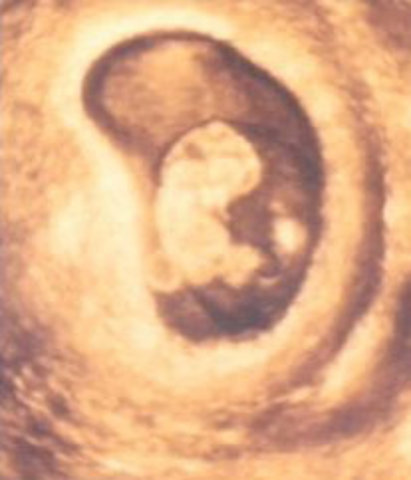

• Month 1

Month 1

-Missed Mentrual Period

-Other signs of pregnancy may not yet be noticebale

• Month 2

Month 2

-Breasts begin to swell.

-Pressure on bladder from enlarging uterus results in need to urinate more often

-Possible nausea(morning sickness)

-Fatigue is common

• Month 3

Month 3

-Breasts become firmer and fuller,may ache.

-Nausea,fatigue,and frequent urination may continue

-Abdomen becomes slightly larger.The uterus is about the size of an orange